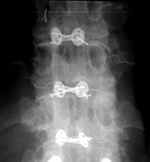

| Pedicle fixation screws and rods |

| 20 year-old woman with L1 vertebral body compression fracture treated with T12-L2 posterior spinal fusion using pedicle screws at T12 and L2 with connecting rods on each side. |